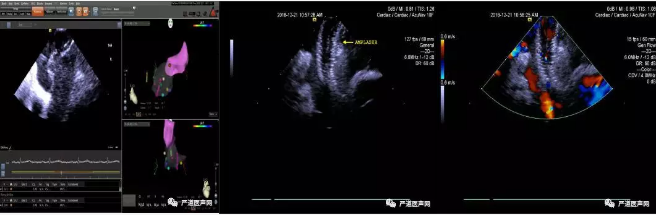

3D-ICE指导ASD封堵过程

12月21日晨07:30,张玉顺教授团队早早来到介入手术室,大家提前准备好各种抢救设备,做好每个环节的准备工作,08:00手术正式开始。台上所有手术人员忙而有序,紧密配合;张教授聚精会神,紧盯屏幕,用娴熟的技术操作着CartoSound 3D-ICE导管,精确地显示了房间隔膨出瘤的大小、幅度及瘤壁上的筛孔,并应用强生公司CARTO 3三维电生理导航系统结合CartoSound 3D-ICE导管精准还原6处缺损的三维空间位置;在3D-ICE指导下,反复调整导丝、导管的走向,如同在梅花针孔中央穿针引线,精准过房间隔膨出瘤中心位置的小缺损后,放置一枚40mm特殊Amplazer筛孔ASD封堵器,将瘤壁上所有的筛孔完美封堵,手术全程历时仅半小时左右,赢得了手术台下医务工作者的阵阵掌声,台上的患者也不由叫好,发自肺腑地对张教授说:“太感谢您了,张教授!”

房间隔膨出瘤并ASD是一种很少见的先天性房间隔发育异常性疾病,术中膨出瘤大小及缺损的大小、数目的判断对封堵器的选择十分重要。3D-ICE能提供更高的图像质量,多角度多扇面地分析感兴趣结构,同时提供缺损实时的三维空间位置,为整台手术提供更详尽的信息,为手术顺利进展保驾护航,缩短手术时间,减少射线暴露,为广大该类患者带来福音!